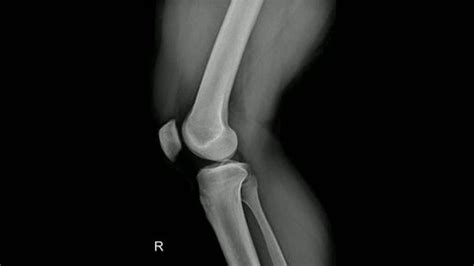

Learn how to interpret a lateral knee X-ray with our expert guide. We cover essential diagnostic views, anatomy identification, and common findings like joint effusions or fractures. Improve your radiographic assessment skills and clinical accuracy when evaluating knee pain, bone abnormalities, and joint health through high-quality imaging analysis and standard orthopaedic positioning techniques.